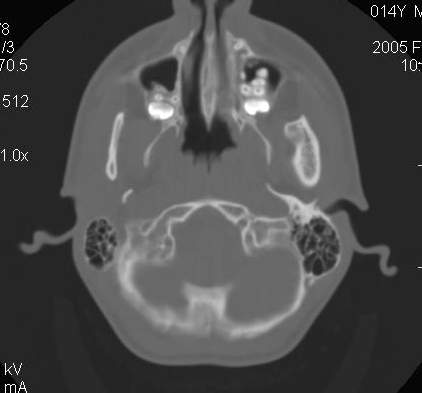

Пациент В., 13 лет. Диагноз: Костный анкилоз левого височно-нижнечелюстного сустава (ВНЧС), левосторонняя микрогения. Болеет с 2-х летнего возраста. Возможная причина развития анкилоза – воспалительный процесс (в первые 1,5 года жизни часто болел простудными заболеваниями, травму родители отрицают). В 3 и 5 лет проводилась редрессация – безуспешно.Прилагаются: ортопантомограмма, кадры СКТ с 3Д реконструкцией. Вопросы: определение тактики лечения – вид и сроки реконструктивно-пластической операции (этапов операции), а именно – неоартропластики и устранения микрогении, медикаментозная терапия в до- и послеоперационный период, ортодонтическое лечение.